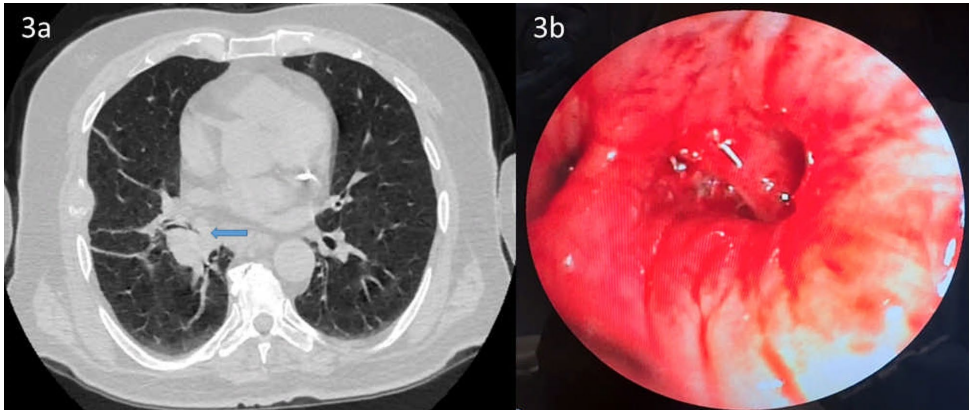

某医疗机构的研究团队在《BMC Pulmonary Medicine》发表的研究,通过3例典型病例的系统分析,为这一临床困境提供了重要见解。研究纳入3例因气道阻塞出现严重呼吸困难的患者,其中2例为冠脉支架术后,1例为外周动脉支架术后,均需持续DAPT治疗。研究团队在完备的止血准备下,使用1.8 mm活检钳实施EBB,所有病例仅出现1级出血(轻度出血仅需吸引),最终均成功获得病理诊断(2例鳞癌,1例肺腺癌复发),未发生严重并发症。

关键技术方法包括:① 局部应用4℃冷生理盐水和稀释肾上腺素(1:10,000)预防出血;② 使用Fujinon EB-530T支气管镜配合1.8 mm活检钳精确取材;③ 持续心电监护下操作;④ 预先备齐止血球囊、介入放射学支持等应急方案。病例均来自临床急症队列,具有明确的手术指征。

结论强调,对于DAPT治疗的气道阻塞患者,当诊断获益大于风险时,EBB可作为安全选择。这为制定支气管镜操作指南提供了III级证据,建议未来开展前瞻性研究确立标准化方案。研究同时指出需警惕肾上腺素的心脏副作用,强调持续监护的重要性。这一发现对优化心血管高风险患者的呼吸道病变管理策略具有重要临床价值。